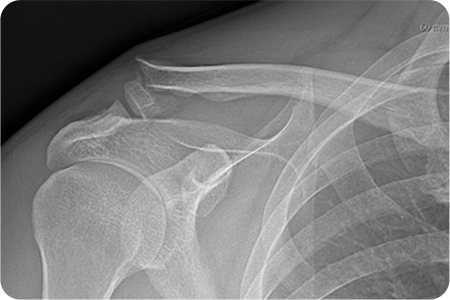

X-ray 및 CT를 통해 골절 형태와 전위 정도를 확인합니다.

쇄골 위쪽을 따라 약 5~8cm 정도 절개하여

골절 부위를 노출합니다. 정복과 고정을 시행하고

절개 부위를 봉합합니다. 수술 후 일정 기간 동안

팔의 움직임을 제한해 뼈가 안정적으로 붙도록 합니다.